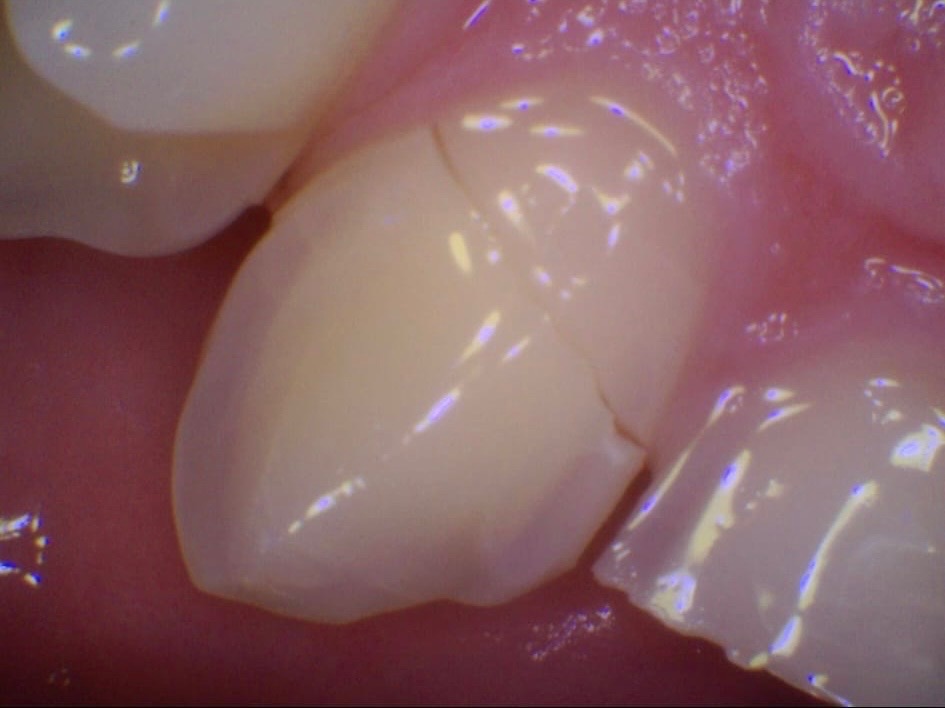

Kaiden suffered a bruised cheekbone, a black eye, concussion and extensive trauma to his teeth.

Altogether, he has six broken teeth.

In the last 24 hours, Kaiden has seen three different dentists. All of them have said this is an extremely severe case of trauma. One dentist, with 20 years of experience, said she had never seen injuries like this from football—only from major accidents.